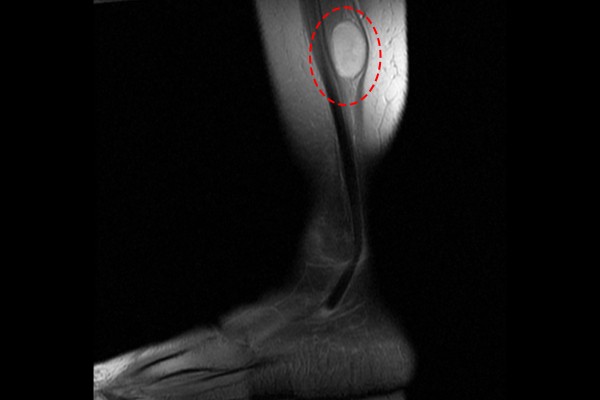

환자분의 증상과 촉진, 이학적 검사 결과를 보았을 때 신경에 종양이 생긴것을 의심하게 되었고, 정확한 확인을 위해 조영제를 사용한 MRI 검사를 진행하였습니다. MRI 검사 결과, 비골신경이라고 하는 발쪽으로 가는 피부 감각신경에 종양이 생긴 것이 확인되었습니다.

b1d6a7ed823268faf8290a31a2d8a8bb_1765960554_9333.jpg

측면에서도 역시 종양이 확인되었고,